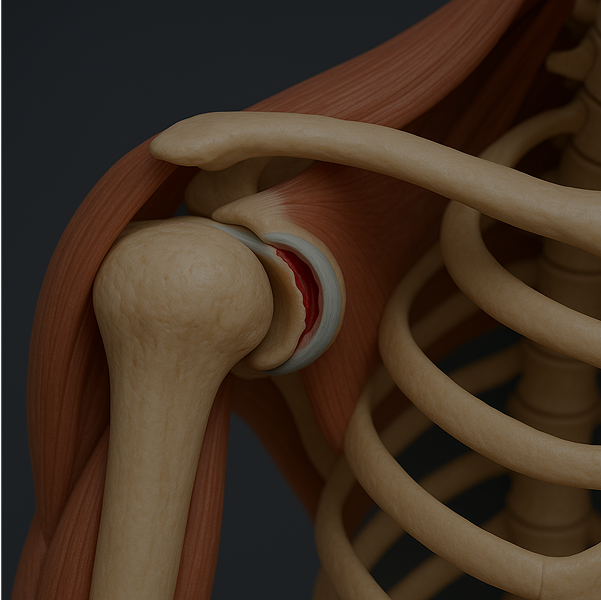

The shoulder is a complex joint made up of various structures that can become injured or inflamed.

Common causes of shoulder pain include

or tears

or adhesive capsulitis

Identifying the root cause of your shoulder pain is essential.